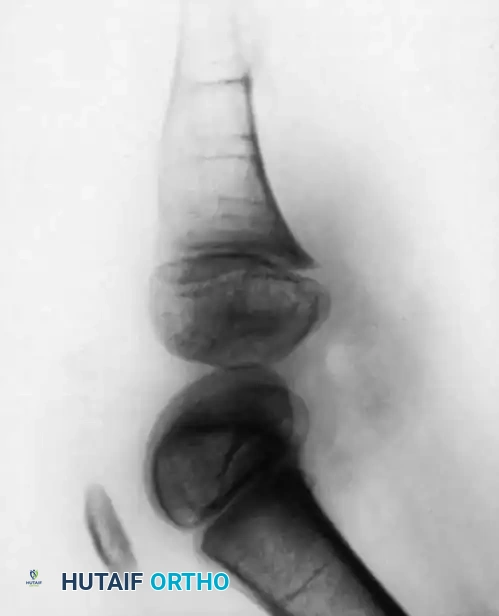

- Type 1B Deformity: There is no radiographic evidence of an ossified tibia; however, the distal femoral epiphysis appears more normal in size and shape. This distinction is critical because Type 1B deformities possess a proximal tibial cartilaginous anlage that can be expected to ossify over time. Modern imaging techniques, such as high-resolution ultrasound and MRI, are mandatory to identify this cartilaginous anlage.

- Type 2 Deformity: A proximal tibia of varying size is present and ossified at birth. The fibula is usually normal in size, but the fibular head is proximally dislocated.

- Type 3 Deformity: The proximal tibia is not radiographically visible, but the distal tibial epiphysis is present. This is an exceptionally rare variant. The distal femoral epiphysis is usually well-formed, but the upper end of the fibula is proximally dislocated, leading to profound knee instability.

In older children, the proximal tibial anlage may be palpable upon deep clinical examination, even if it is not radiographically visible. The knee is generally flexed, and in more severe deformities, profound quadriceps insufficiency causes an absolute lack of active knee extension.

Clinical Pearl: Careful clinical evaluation of the quadriceps extensor mechanism is paramount. The presence or absence of active quadriceps function has the most significant prognostic value regarding the potential for successful surgical reconstruction of the knee joint.